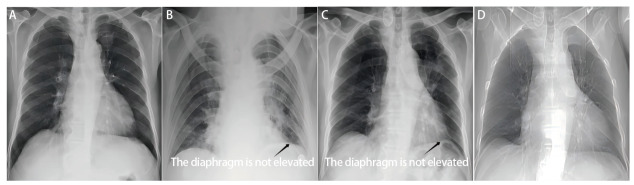

Background: Video-assisted thoracoscopic surgery (VATS) lobectomy is the primary surgical treatment for lung cancer. A significant factor affecting postoperative recovery is prolonged air leak (PAL). Despite numerous clinical strategies could prevent and manage postoperative PAL, its incidence remains high. Phrenic nerve cryotherapy (PNC) temporarily inhibits phrenic nerve function, causing diaphragm elevation, which reduces thoracic cavity volume, enhances pleural apposition, and mitigates air leakage. This study investigates the efficacy of PNC in preventing postoperative PAL during VATS lobectomy.

Results: The baseline clinical characteristics were comparable between the two groups (P>0.05). The incidence of pulmonary air leakage at 24 h after surgery (31.5% vs 29.6%) and the incidence of postoperative PAL (20.4% vs 14.8%) showed no significant differences between the two groups (P>0.05). The intraoperative air leak test to 24 hours after surgery revealed that air leakage ceased in 8 cases (32.0%) in the control group, compared to 14 cases (46.7%) in the experimental group. Moreover, during the progression from air leakage at 24 hours post-surgery to postoperative PAL, air leakage ceased in 6 cases (35.3%) in the control group and 8 cases (50.0%) in the experimental group, with a statistically significant difference (P<0.001). Compared to the control group, the patients in the experimental group exhibited more pronounced postoperative diaphragmatic elevation that recovered to a slightly higher than preoperative level by 3 mon after surgery.